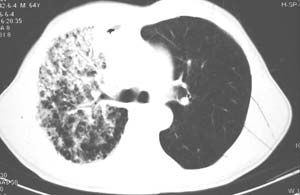

右肺上叶大片片状、网格状及索条致密影,前半部密实向后逐渐疏松,其内参杂斑点状小结节,密度不均匀,内见含气支气管像,纵隔内见肿大淋巴结,其他肺呈弥漫性小叶中心性性肺气肿改变,结合男 64  咳血,咳痰,发热3天,血象1.2万。考虑:1 慢性支气管炎、肺气肿合并右上肺感染。2 不除外结核合并感染的可能。

影像表现:肺窗示右肺上中叶均可见小片、条索状、小结状密度增高影,可见支气管充气相,小叶间隔增厚,支气管通畅,余肺未见明显异常。纵隔窗示4r可见小淋巴结融合,无明显肿大,右侧示少量胸腔积液。

诊断:提示右肺上中叶感染性病变,tb可能大。

右侧胸阔塌陷,纵隔右移。右上肺大片状高密度影,沿支气管血管束走行,内见点状钙化;支气管充气征阳性,支气管呈柱状扩张;胸膜下小叶间隔增厚;右侧后胸壁内侧见带状水样密度影;纵隔淋巴结增大。

考虑:①右上叶陈旧性结核合并感染可能大。②右侧少量胸水。

影像学表现:右肺上叶大片状、网格状及索条致密影,前半部密实向后逐渐疏松,其内参杂斑点状小结节,密度不均匀,内见含气支气管像,纵隔内见肿大淋巴结.

综上,以右上肺tb(干酪性肺炎)首先考虑.当然大叶性肺炎不能除外.(血象不是特别高,纵隔内淋巴结肿大,也不甚支持.).如果经积极抗感染治疗,病灶明显好转.更能明确为大叶性肺炎.也不能明确排除肺ca.建议痰培养和纤支镜.